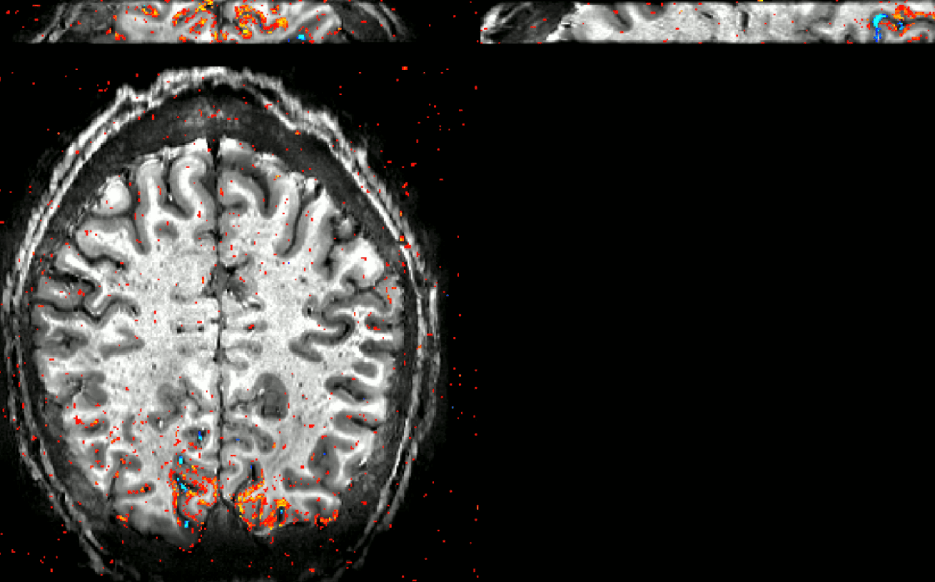

- Ruediger Strinberg and Tony Stoecker implemented a VASO sequence with segmented 3D-EPI readout for SIEMENS VE systems.

Data of this figure were acquired with Stirnberg’s sequence at the 7T Terra at NIH.